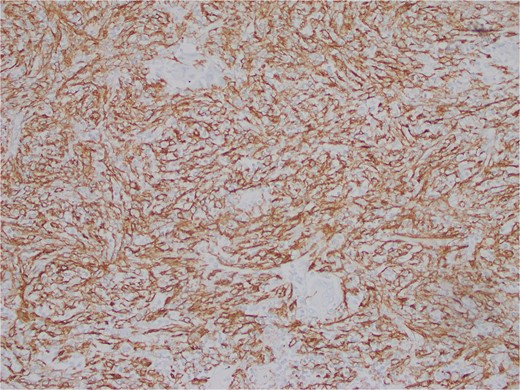

The interspersed lymphoid elements comprised of relatively B-cell rich nodules and numerous background T-cells. An atypical, spindled population is highlighted by chromogenic in-situ hybridization (CISH) for EBV-encoded RNA (EBER) (Fig. 5), EBV Latent Membrane Protein (LMP)1, smooth muscle actin, and clusterin (Fig. 6). Ki-67 showcased interspersed germinal centers within the inflammatory lesion and in the adjacent splenic tissue. The Ki-67 proliferation rate was otherwise low. CD31 depicted variable vascular inflammatory elements. S100 displayed scattered positivity. CD68 revealed numerous histiocytic elements. Limited PU.1 staining was observed. CD138 and IgG indicated numerous interspersed plasma cells with a focal slight increase in IgG4 positivity. CD21, CD23, and CD25 illustrated a dendritic meshwork associated with interspersed follicles. CD4 indicated numerous inflammatory elements. CD8 highlighted light-scattered T-cells and splenic sinusoids from the background spleen. Sinusoids were absent from the inflammatory lesion. Ultra-sensitive CISH dual stain for kappa and lambda revealed polytypic B-cells and plasma cells. These findings are diagnostic of an EBV+ inflammatory follicular dendritic cell/fibroblastic reticular cell tumor, according to International Consensus Classification (2022).

Atypical, spindled population is highlighted by clusterin (Clusterin 400X).